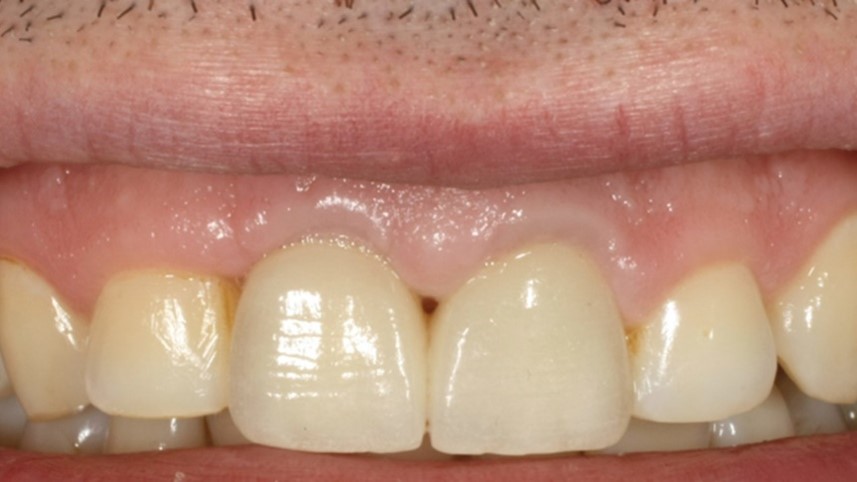

Il caso clinico del Professor Soardi illustra chiaramente i risultati estremamente interessanti che si riescono ad ottenere attraverso il protocollo Open Barrier Tecnique, attraverso un approccio minimamente invasivo ed utilizzando materiali e metodi testati. Come potrete vedere dal risultato finale anche una situazione così difficilmente recuperabile, in altissima zona estetica, può essere gestita e risolta ottimamente.

Immagine clinica iniziale ed evidenza radiografica del riassorbimento radicolare